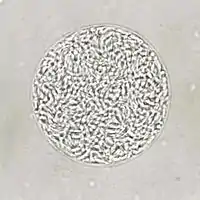

Giemsa stained T. gondii tachyzoites, 1000× magnification

Tachyzoites

Motile, and quickly multiplying, tachyzoites are responsible for expanding the population of the parasite in the host.[29][30]:19

When a host consumes a tissue cyst (containing bradyzoites) or an oocyst (containing sporozoites), the bradyzoites or sporozoites stage-convert into tachyzoites upon infecting the intestinal epithelium of the host.[30]:359 During the initial acute period of infection, tachyzoites spread throughout the body via the blood stream.[30]:39–40

During the later, latent (chronic) stages of infection, tachyzoites stage-convert to bradyzoites to form tissue cysts.